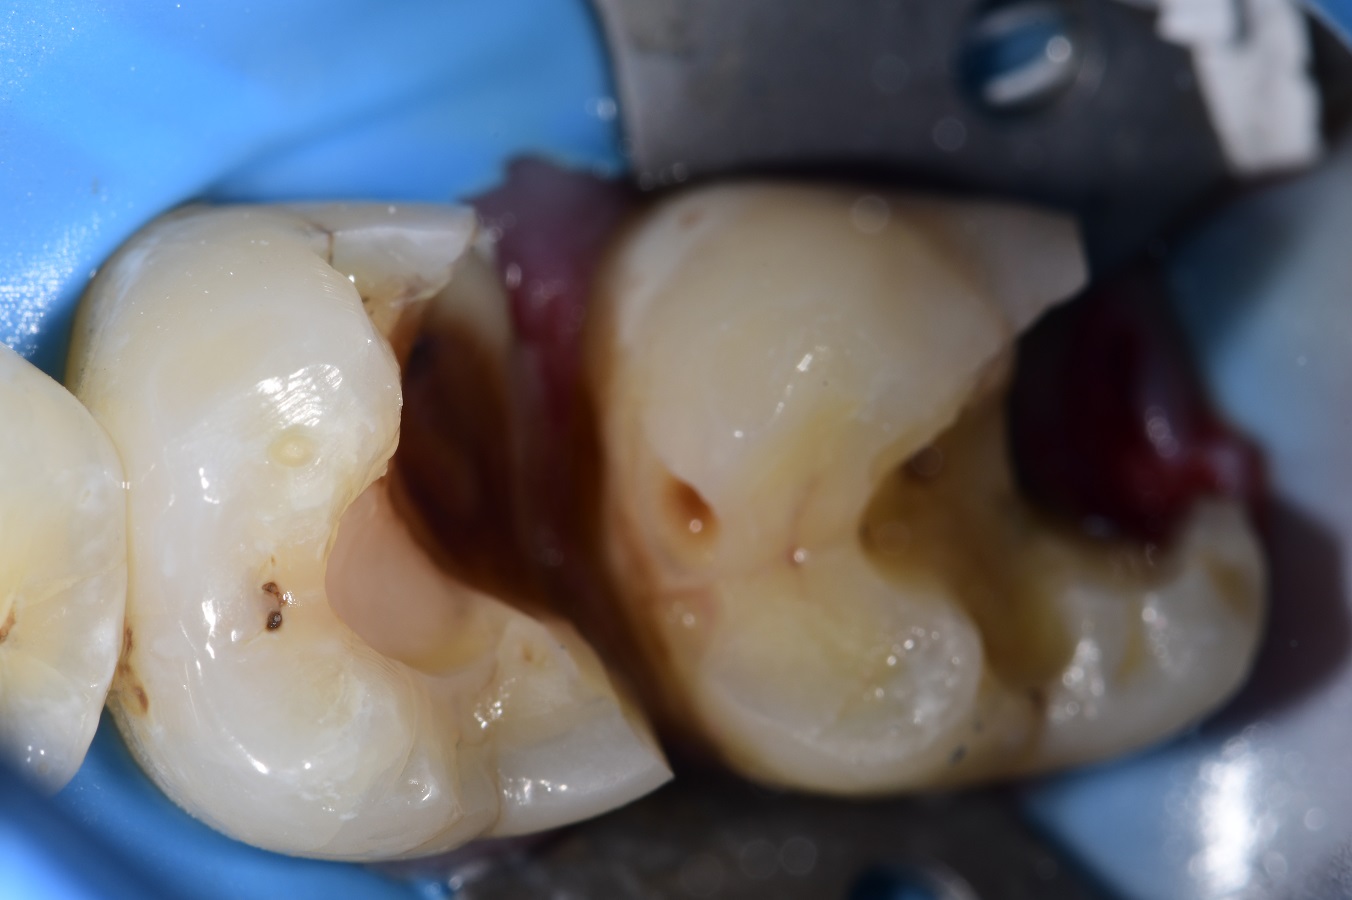

Figure 1 from Orthodontic protraction of the third molars to the posterior teeth missing area